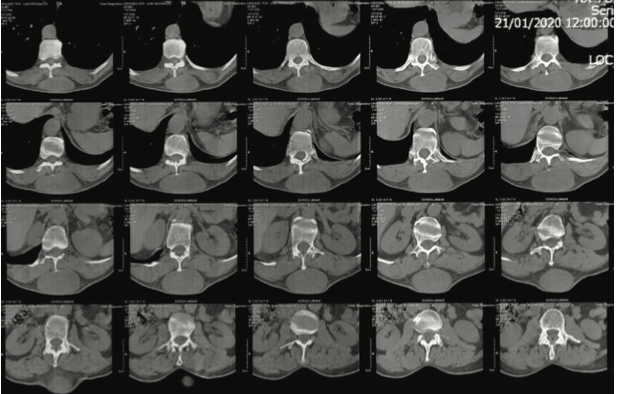

Tomografía de columna dorsolumbar: se evidencia co- lección liquida a nivel de tejidos blandos subcutáneos posterior de la región dorso lumbar de T10 a L1 de 7.3x3.9x12.4cm con un volumen de 184cc. Los bordes son bien definidos y las paredes son delgadas, con un gro- sor de 2.3mm, los cuales, tras la aplicación de medio de contraste, muestra realce sugestivo. No hay invasión de estructuras óseas o músculos paravertebrales (figura 2).